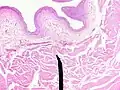

Microanatomy

When viewed under a microscope, the bladder can be seen to have an inner lining (called epithelium), three layers of muscle fibres, and an outer adventitia.[8]

The inner wall of the bladder is called urothelium, a type of transitional epithelium formed by three to six layers of cells; the cells may become more cuboidal or flatter depending on whether the bladder is empty or full.[8] Additionally, these are lined with a mucous membrane consisting of a surface glycocalyx that protects the cells beneath it from urine.[14] The epithelium lies on a thin basement membrane, and a lamina propria.[8] The mucosal lining also offers a urothelial barrier against the passing of infections.[15]

These layers are surrounded by three layers of muscle fibres arranged as an inner layer of fibres orientated longitudinally, a middle layer of circular fibres, and an outermost layer of longitudinal fibres; these form the detrusor muscle, which can be seen with the naked eye.[8]

The outside of the bladder is protected by a serous membrane called adventitia.[8][16]

Vertical section of bladder wall -

Layers of the bladder wall and cross-section of the detrusor muscle

Anatomy of the male bladder, showing transitional epithelium and part of the wall in a histological cut-out